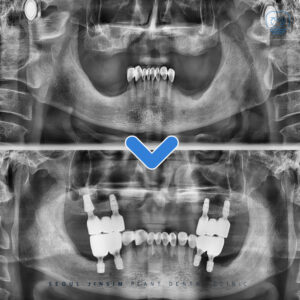

장안구치과 재신경치료 잘하는 치과 ,장안구치과 안녕하세요 수원 장안구에 위치하고 있는 장안구치과 서울진심플란트치과입니다. , 오늘은 오른쪽 아래 큰 어금니에 재신경치료를 진행하셨던 환자분의 사례를 소개해드리겠습니다. , 과거에 신경치료를 받았지만 이후 크라운 수복…